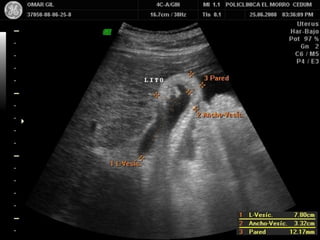

LITO

NIVEL Y CAUSA DE OBSTRUCCION

1. Conducto intrahepatico común

90% de las obstrucciones biliares ocurren a nivel

del conducto distal y producen una dilatación

de la totalidad de su trayecto

Causas mas frecuentes:

Carcinoma pancreático

Coledocolitiasis

Pancreatitis crónica con desarrollo de estenosis